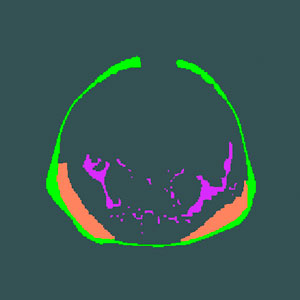

The superficial subcutaneous tissue (green), the deep subcutaneous tissue (orange), and the internal adipose tissue (magenta) of Singaporean infants of three different ethnic backgrounds were measured and compared.

The study investigated differences in three different fat compartments in the abdomen: abdominal superficial subcutaneous tissue, which is located just under the skin and surrounds the abdominal cavity; abdominal deep subcutaneous tissue, which is clearly separated from the superficial fat by a sheath of fibrous tissue and is located on either side of the posterior abdominal wall; and internal adipose tissue — the minute amount of fat that surrounds the abdominal organs.